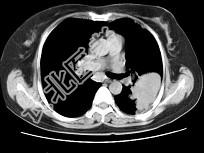

- 单项选择题女,52岁, 左侧背痛1月,胸部CT如图, 最可能的诊断为 ( )

A、左肺中央型肺癌

B、左肺周围型肺癌

C、左肺感染

D、左肺炎性假瘤

E、肺隔离征